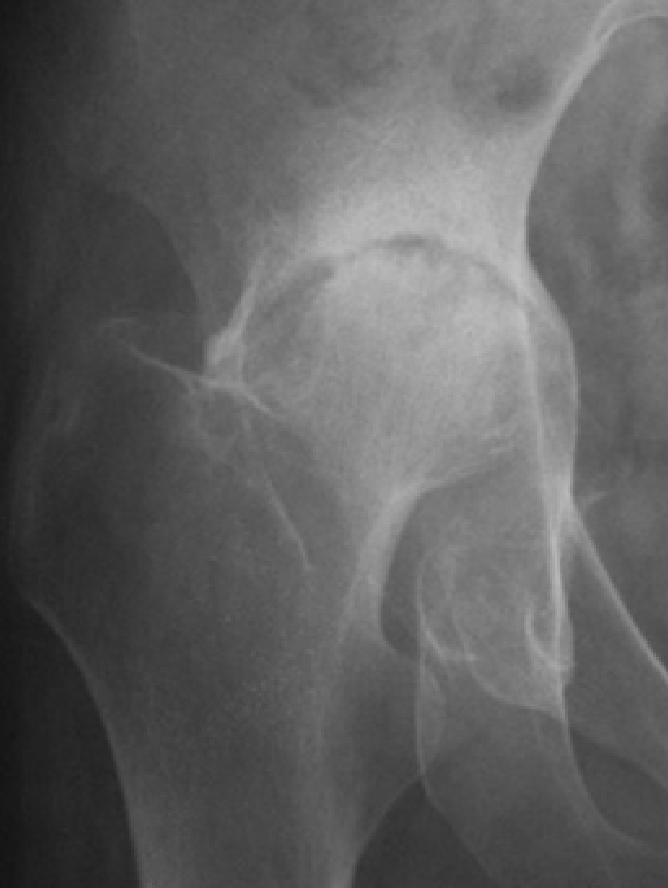

4. 変形性股関節症

変形性股関節症には、一次性と二次性があります。一次性は、長い年月を経てあるいは関節の使いすぎによって軟骨が消耗して起こります。二次性は、乳児期の股関節の脱臼や発育不全などの臼蓋形成不全によって早期から起こる変形性股関節症です。

レントゲンで見ると一次性は、正常な股関節が長い年月や股関節の使い過ぎによって軟骨が消耗して変形性股関節症が発症します(図7)。二次性は、元々臼蓋形成不全により体重がかかる部分が限られており早期なら軟骨が消耗し変形性股関節症になります(図8)。

図7. 一次性の変形性股関節症

長い年月を経て、あるいは関節の使いすぎによって起こる。